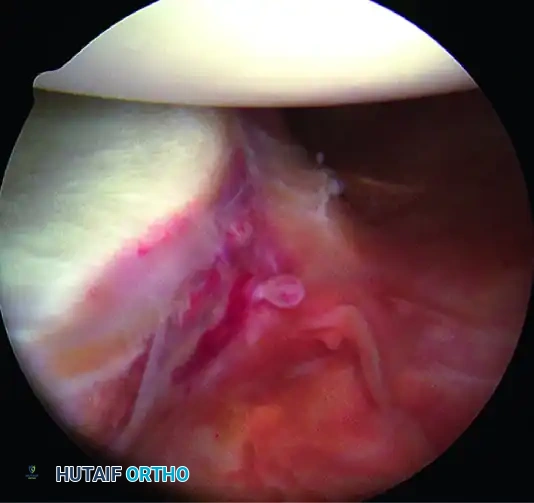

3. Anterior Anchor Placement

Transition to the anterior Bankart repair. The goal is to secure anatomical fixation 2 mm onto the articular surface with a minimum of three (preferably four) suture anchors, spaced 5 to 7 mm apart.

The Inferior Anchor (The Keystone):

The most critical anchor is the most inferior one. Use the 5-o’clock percutaneous portal with a spinal needle for precise trajectory (45-degree angle to the articular surface). Place the spear guide at the 5:30 position, 1 to 2 mm onto the articular cartilage margin. Drill and insert a biocomposite or all-suture anchor (e.g., JuggerKnot).

B, Anchor inserted on articular edge.

4. Suture Passing and Superior Advancement

To eliminate the drive-through sign and restore physiological tension, the capsule must be shifted superiorly and laterally.

- Retrieve the most inferior suture limb out of the posteroinferior cannula using a suture grasper.

- Use a Spectrum suture passer through the anterior cannula to take a substantial (1 cm) bite of the capsule and labrum inferior to the anchor site.

C, A 1-cm capsular bite taken with Spectrum suture passed distal to anchor.